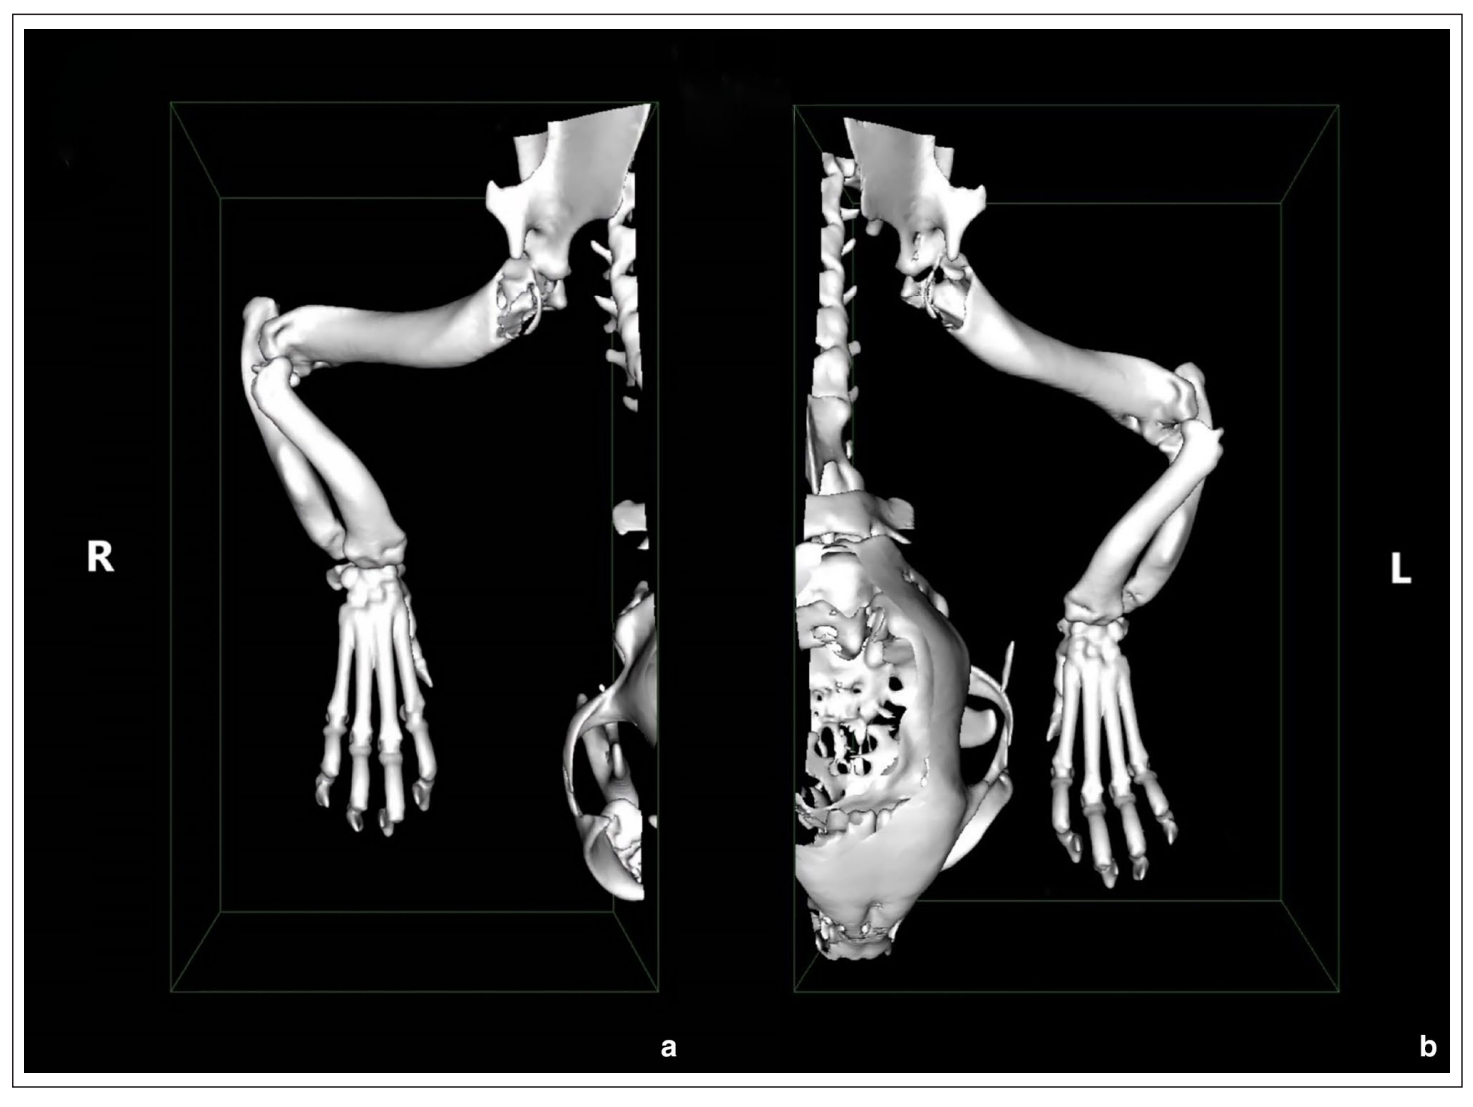

术前CT显示双侧前肢弯曲畸形,包括桡骨向前弯曲、爪子外旋和腕关节内翻。双侧肘关节不匹配和桡骨头半脱位被记录下来,右侧轻微,左侧明显(下图)。诊断为双侧前肢弯曲畸形,推测是由于软骨发育不良导致远端尺骨生长板生长缓慢所致。左前肢桡骨头半脱位和肱尺关节半脱位被认为是跛行的原因。

↑ (a) 右侧和 (b) 左侧前肢的CT三维重建体积的背侧视图。这些图像显示双侧前肢弯曲畸形,包括桡骨向前弯曲、爪子外旋和腕关节内翻。左侧桡骨头的半脱位更为明显。